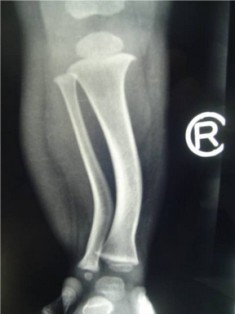

Postero-Medial Bowing of Tibia is a congenital condition characterized by a curvature or bending of the tibia bone, which is one of the two bones in the lower leg. This condition usually becomes apparent during infancy or early childhood. While the

exact cause of this condition is not always known, it is believed to be related to factors affecting fetal bone development.

The most noticeable symptom of Postero-Medial Bowing of Tibia is the

inward curving of the tibia bone, which may lead to a bowlegged appearance. Other symptoms can include uneven leg lengths, difficulty walking or standing, and potential discomfort as the child grows. Diagnosis typically involves a thorough physical examination, medical history review, and often imaging studies such as X-rays.